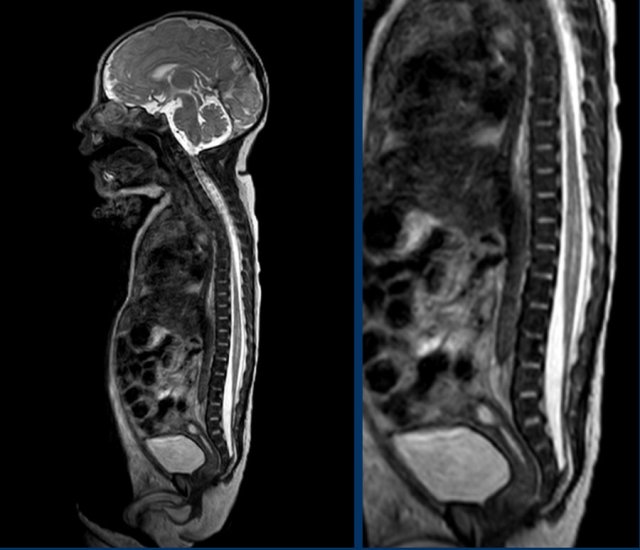

Newborn girl with a cloacal malformation.

The conus medullaris is at L5.

No lipoma visible.

Findings were confirmed at MR imaging which was acquired at the age of 9 months.

Continue with the MR.

MR image at the age of 9 months.

The conus medullaris is now seen at L4.